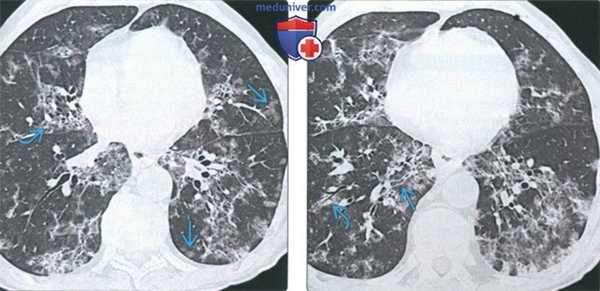

(Слева) На аксиальной КТ без КУ у пациента с перибронхиальным интерстициальным фиброзом определяется утолщение перибронховаскулярных тканей наряду с тракционными бронхоэктазами и воздушными «ловушками». Была выполнена криобиопсия, подтвердился перибронхиальный интерстициальный фиброз.

(Справа) На аксиальной КТ без КУ у пациента с перибронхиальным интерстициальным фиброзом определяется утолщение перибронховаскулярных тканей. Края бронховаскулярных пучков неровные. Определяются также структурные нарушения и слабо выраженные участки «матового стекла» с нечеткими границами в верхней доле левого легкого.

(Слева) На аксиальной КТВР у пациента с перибронхиальным интерстициальным фиброзом определяется утолщение пе-рибронховаскулярных тканей наряду с неравномерным расширением дыхательных путей и тракционными бронхоэктазами, сопоставимыми с легким интерстициальным фиброзом. Обратите внимание на разбросанные воздушные «ловушки».

(Справа) На корональной КТВР у этого же пациента определяются асимметричные структурные нарушения в верхней доле левого легкого, двухсторонняя «мозаичная» картина, утолщение стенок бронхов и тракционные бронхоэктазы.